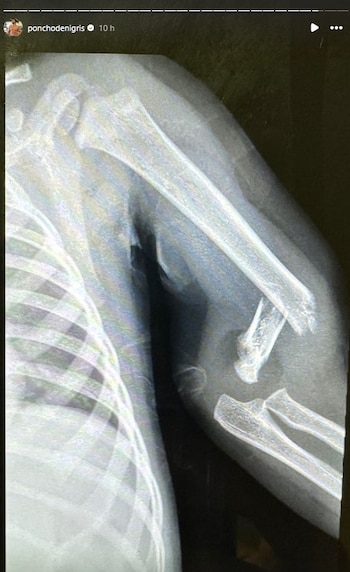

El doctor que atendió a Toñito confirmó que se fracturó su brazo a la altura del codo, por lo que tuvo que ser operado de emergencia.

“Ya lo llevamos al hospital, lo vio el doctor. Yo le sentí el bracito que estaba así zafado y fue un accidente que pasó y ya (...) lo van a tener que operar, ponerle clavos y todo eso y ahorita nos vamos a ir a dormir al hospital”, dijo.

El menor fue intervenido quirúrgicamente alrededor de las 21:00 horas y afortunadamente la operación fue todo un éxito, así lo dio a conocer Poncho de Nigris a través de sus historias de Instagram.

Mientras tanto, Marcela Mistral pidió oraciones por la pronta recuperación de su bebé e informó que ya despertó de la anestesia: “Nos dieron permiso de darle agua y leche. Con eso se tranquilizó abismalmente (...) la cirugía fue un éxito a pesar de lo aparatoso por su edad”.